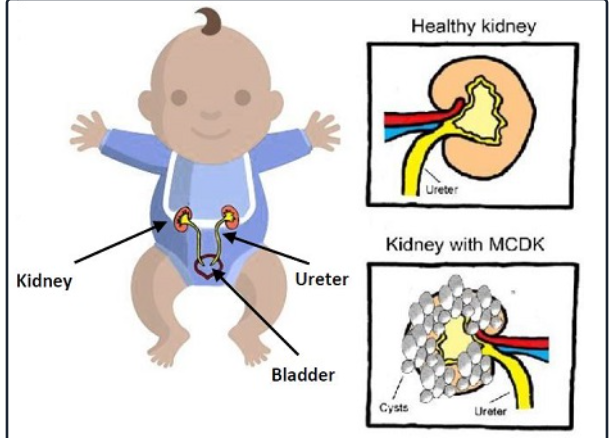

Loạn sản thận là tình trạng thận phát triển bất thường từ giai đoạn bào thai, làm giảm hoặc mất khả năng đảm nhiệm chức năng lọc máu của thận đó. Tuy nhiên, điều quyết định mức độ ảnh hưởng không nằm ở tên gọi, mà nằm ở:

- Loạn sản xảy ra ở một bên hay hai bên thận

- Mức độ tổn thương của thận bị ảnh hưởng

- Khả năng bù trừ của thận còn lại

Loạn sản thận là bất thường cấu trúc, nên thường được nghi ngờ trong siêu âm hình thái quý 2, khoảng tuần 20–24.

- Thận tăng âm bất thường

- Cấu trúc thận không đồng nhất

- Ranh giới vỏ – tủy mờ

- Hình dạng thận biến đổi